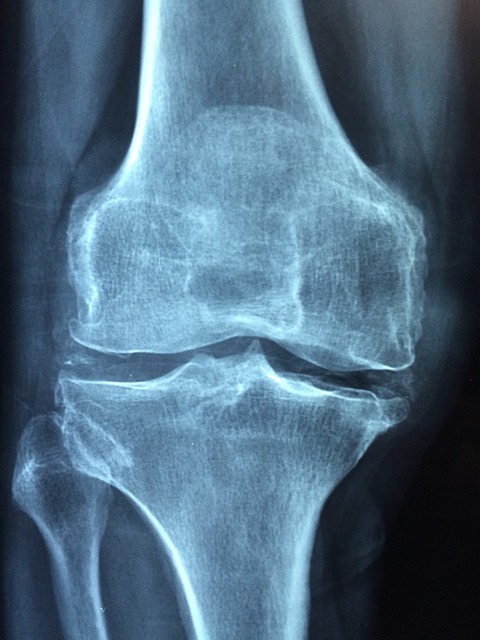

10. 뻣뻣함 및 뚝뚝 소리

관절이 뻣뻣해지고 움직일 때 뚝뚝 소리가 난다면, 이는 관절 마찰이나 연골 손상의 신호일 수 있습니다. 이러한 증상은 초기에는 무시되기 쉽지만, 점차 심각한 문제로 이어질 수 있습니다.